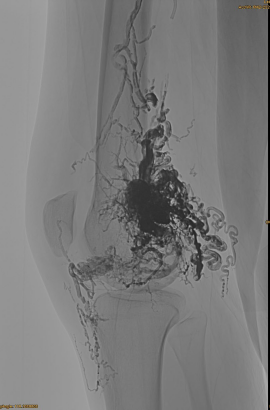

المعلومات الأساسية للمريض: أنثى ، 36 سنة ؛ AVM Pelvis ، HIP ، الركبة ، OSG اليسرى ، متعددة pre -.

المنتجات المستخدمة: 3pcs lava-34،14pcs lava-18.

من قبل ، onyx القديمة من قبل- الانصمام:

DSA الأولي:

النتيجة النهائية:

بالكاد أي تدفق وريدي:

المرحلة المتأخرة ، embo آخر ضروري ، ولكن أفضل بكثير: